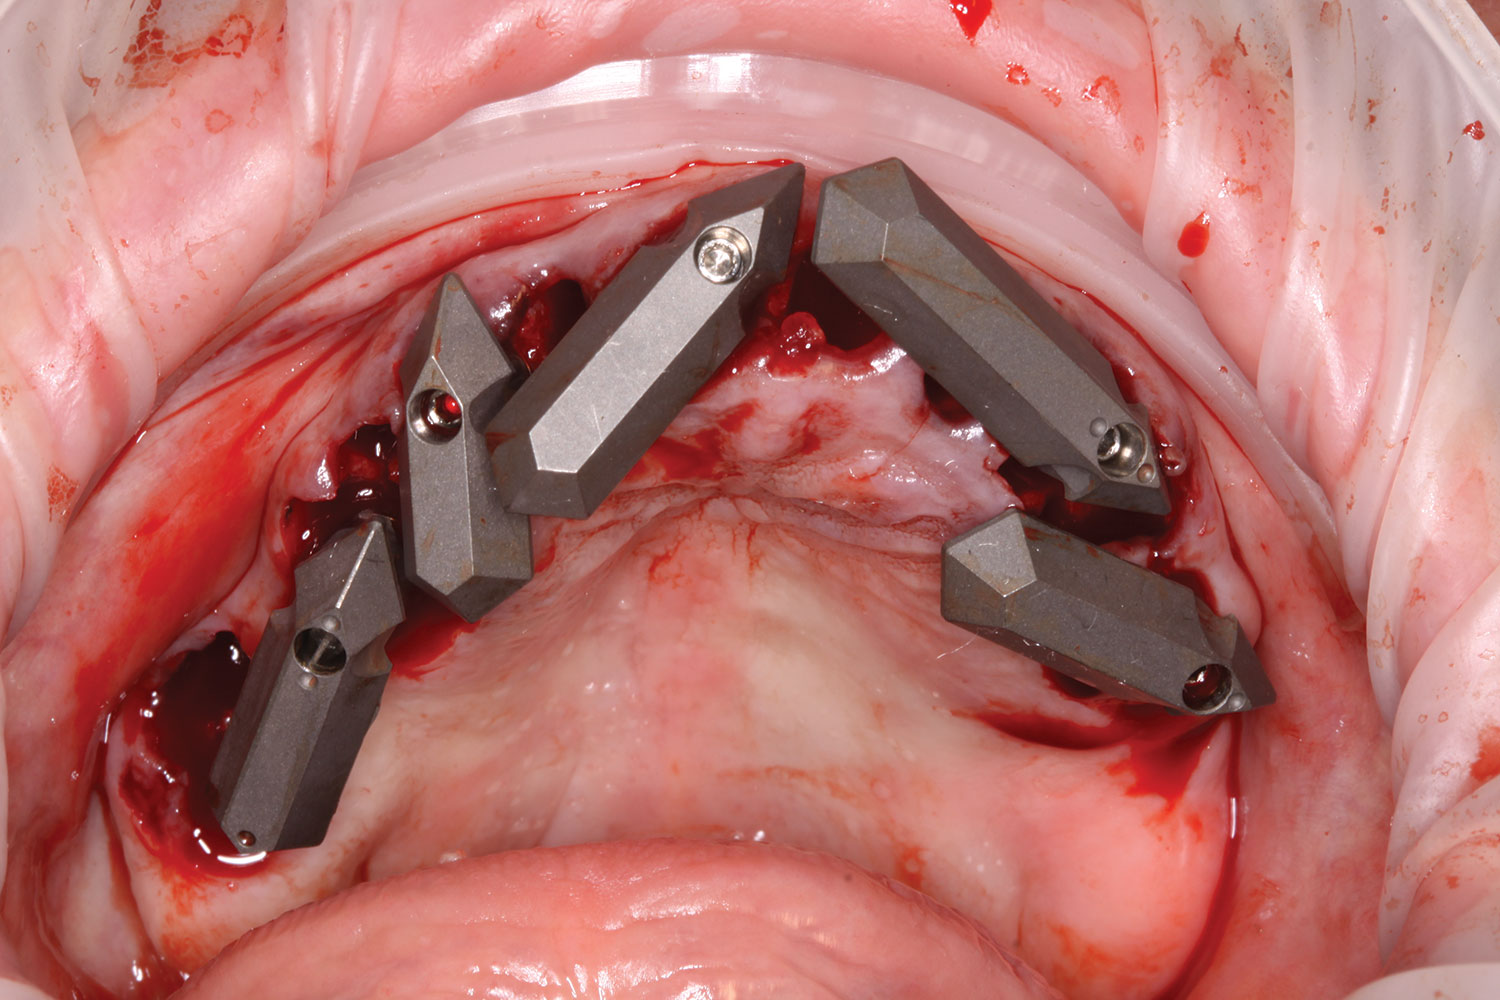

A week later the patient presented for surgery for extraction and replacement of her existing maxillary dentition with implants and a screw-retained provisional implant restoration. Teeth Nos. 2, 4, and 6 through 11, 13, and 14 were carefully extracted with attention paid to retaining site dimensions. Immediate implants were inserted into sites Nos. 4, 6, 8, 11, and 13 with high insertion torques in excess of

40 Ncm. Subsequently, multi-unit abutments were placed on all the implants and torqued to 30 Ncm, and scan gauges were placed on implant Nos. 8 and 11 (Figure 12 and Figure 13).

Fig 12. Partial extractions and placement of implants and multi-unit abutments.

Figure 12

Fig 13. Initial scan of scan gauges with residual teeth retained for reference.

Figure 13